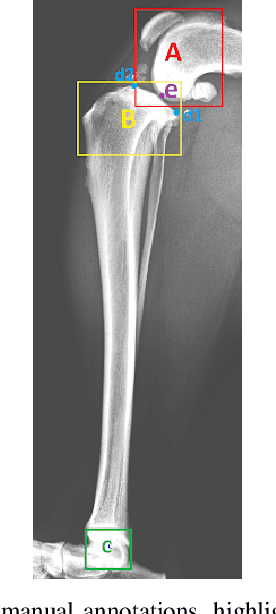

Abstract:Stifle joint issues are a major cause of lameness in dogs and it can be a significant marker for various forms of diseases or injuries. A known Tibial Plateau Angle (TPA) helps in the reduction of the diagnosis time of the cause. With the state of the art object detection algorithm YOLO, and its variants, this paper delves into identifying joints, their centroids and other regions of interest to draw multiple line axes and finally calculating the TPA. The methods investigated predicts successfully the TPA within the normal range for 80 percent of the images.